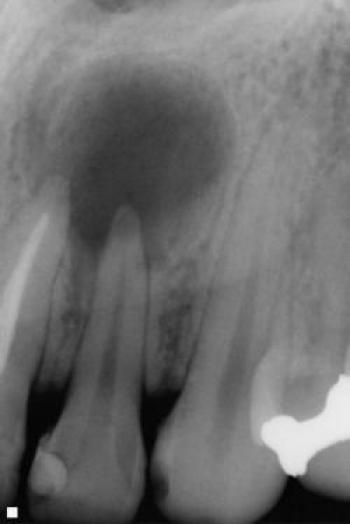

Оказавшись в нерве, инфекция может спуститься к верхушкам корней и выйти за пределы каналов зуба в окружающую зуб ткань - периодонт. Организм сразу включает защитную реакцию и строит вокруг очага инфекции непроницаемую мембрану, залючая ее в герметичный "мешок" и отделяя ее от стерильных тканей. Это и есть киста зуба, в которой продолжают жить и размножаться бактерии, киста растет дальше. Еще одной причиной образования кисты под зубом может быть некачественное ранее проведенное лечение каналов.

Киста зуба может не давать ни одного из вышеперечисленных симптомов, развиваться безболезненно. Тем не менее кисту зуба необходимо лечить. Такие кисты, как правило, выявляются случайно на рентгеновских снимках.

Лечить кисту зуба большого размера не имеет смысла. Зуб с большой кистой подлежит удалению. По прошествии 2-3 месяцев после удаления отсутствующий зуб восстанавливается с помощью зубного имплантата.